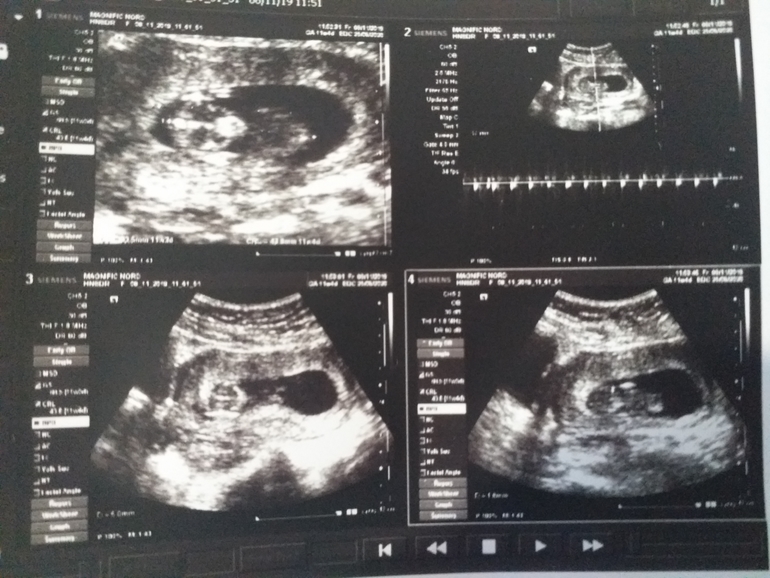

Можно поинтересоваться у вас по УЗИ небольшое пя по виду, вам ничего не говорили , не помните размены случайно на 11 недели у меня 11 неделя мне кажется пя небольшое для ребёнка